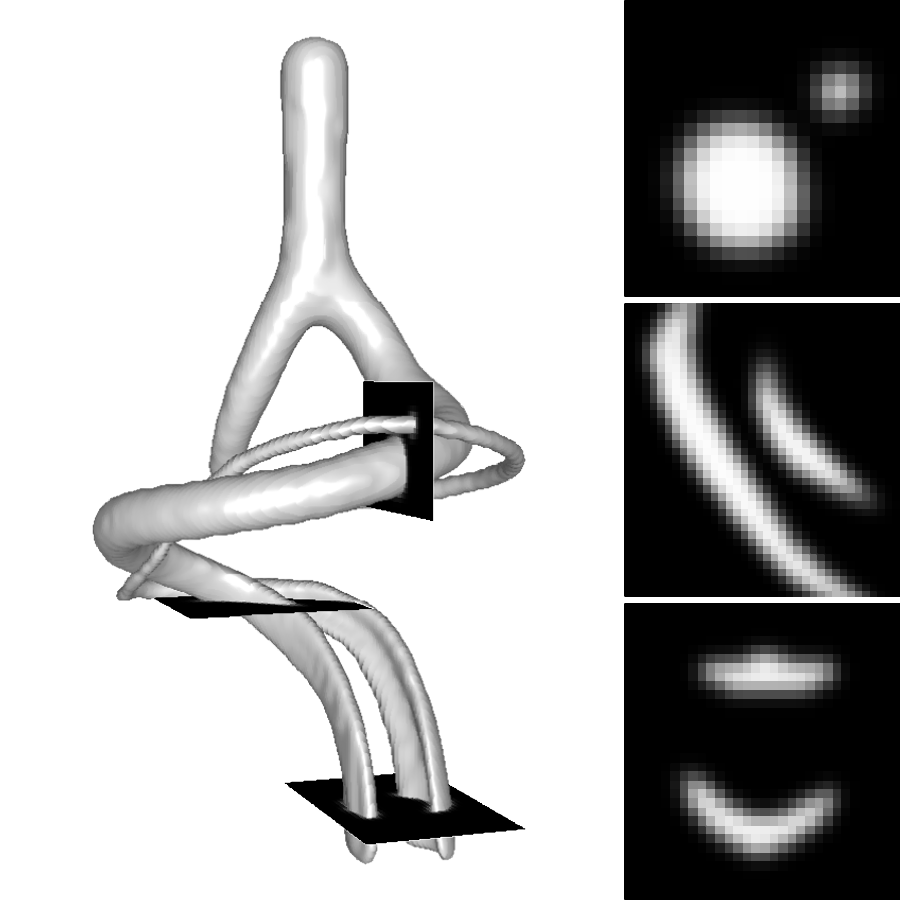

A 3D hand-crafted tortuous and convoluted phantom (HCP) is designed to account for complex vessel patterns, i.e. branching, kissing vessels, scale and shape variations induced by pathologies. Also a set of 20 synthetic vascular trees (SVT) ( voxels) were generated using VascuSynth [10] considering two levels of additional noise (N1: + Shadows: 1 + SaltPepper: ; N2: + Shadows: 1 + SaltPepper: ). Together with the synthetic data, a cerebral Phase Contrast MRI (PC) ( mm), a cerebral Time of Flight MRI (TOF) ( mm) and a carotid CTA ( mm) were used. Vascular network ground-truths (GT) are given in the form of connected raster centerlines for all the synthetic images and for both TOF and CTA.

3.2 Connected Geodesic Paths as Vascular Tree

Representative examples of degraded synthetic images from SVT and the respective GT are shown in fig. 4 together with the connected graphs extracted by VTrails. Analogously, the same set of images are reported for the real images TOF and CTA in fig. 4. Qualitatively, the extracted set of connected geodesic paths shows remarkable matching with the provided GT in all cases. First, we verify the acyclic nature of the graph. We found no cycles, degenerate graphs and unconnected nodes, meaning that the extracted connected geodesic paths represent a connected geodesic tree. Precision and recall are then evaluated for the identified branches. Also, error distances are determined as the connected tree’s binary distance map evaluated at GT. Average errors () precision and recall are reported (meanSD) in table 1. Note that no pruning of any spurious branches is performed in the analysis.